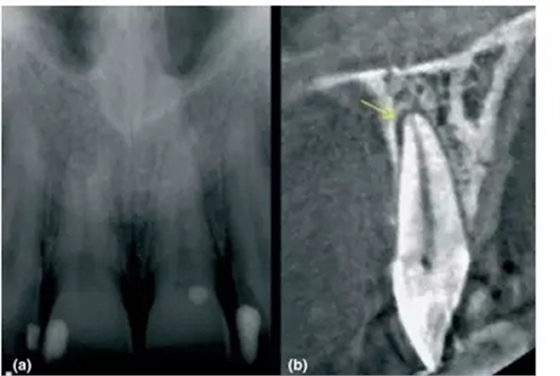

1,根尖周炎的探測(cè)

a- 11和21根尖影像無(wú)異常,但患者主訴該區(qū)有間歇的鈍痛

b-CBCT顯示21腭側(cè)有透射影,根管治療后患者癥狀消失

前文中已經(jīng)討論了能顯示在傳統(tǒng)X片上根尖周暗影,其范圍一定侵犯到皮質(zhì)骨。然而CBCT卻能精準(zhǔn)探測(cè)只局限于松質(zhì)骨中的病損,讓臨床醫(yī)生能早診斷、早處理,提高現(xiàn)代牙體牙髓治療的成功率。